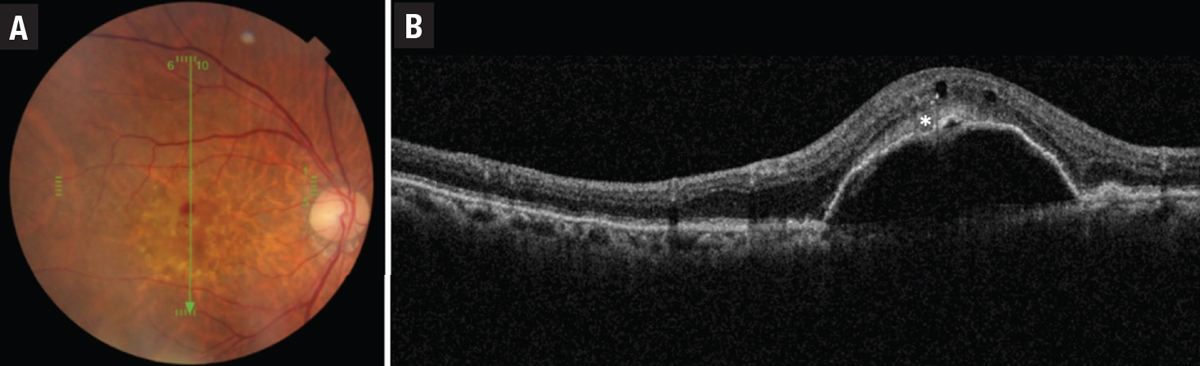

| Figure 4. An example of a type 3 macular neovascular membrane. A) Fundus photograph shows intraretinal hemorrhage and pseudodrusen. B) Corresponding optical coherence tomography B-scan shows serous pigment epithelial detachment, intraretinal fluid and subretinal hyperreflective density (asterisk). |

• Type 3 MNV, also known as retinal angiomatous proliferation (RAP), differs from type 1 and 2 lesions as the neovascularization is thought to originate from within the retina itself and is often associated with intraretinal rather than subretinal fluid and hemorrhage. As it progresses, type 3 MNV forms a retinal-retinal anastomosis and invades the subretinal space with the development of a serous PED (Figure 4). Finally, a retinal-choroidal anastomosis occurs through the vertex of the PED with the development of CNV. Early type 3 lesions may present as a focal area of hyperfluorescence on FA. As the lesion progresses, a serous PED or CNV may appear on FA.